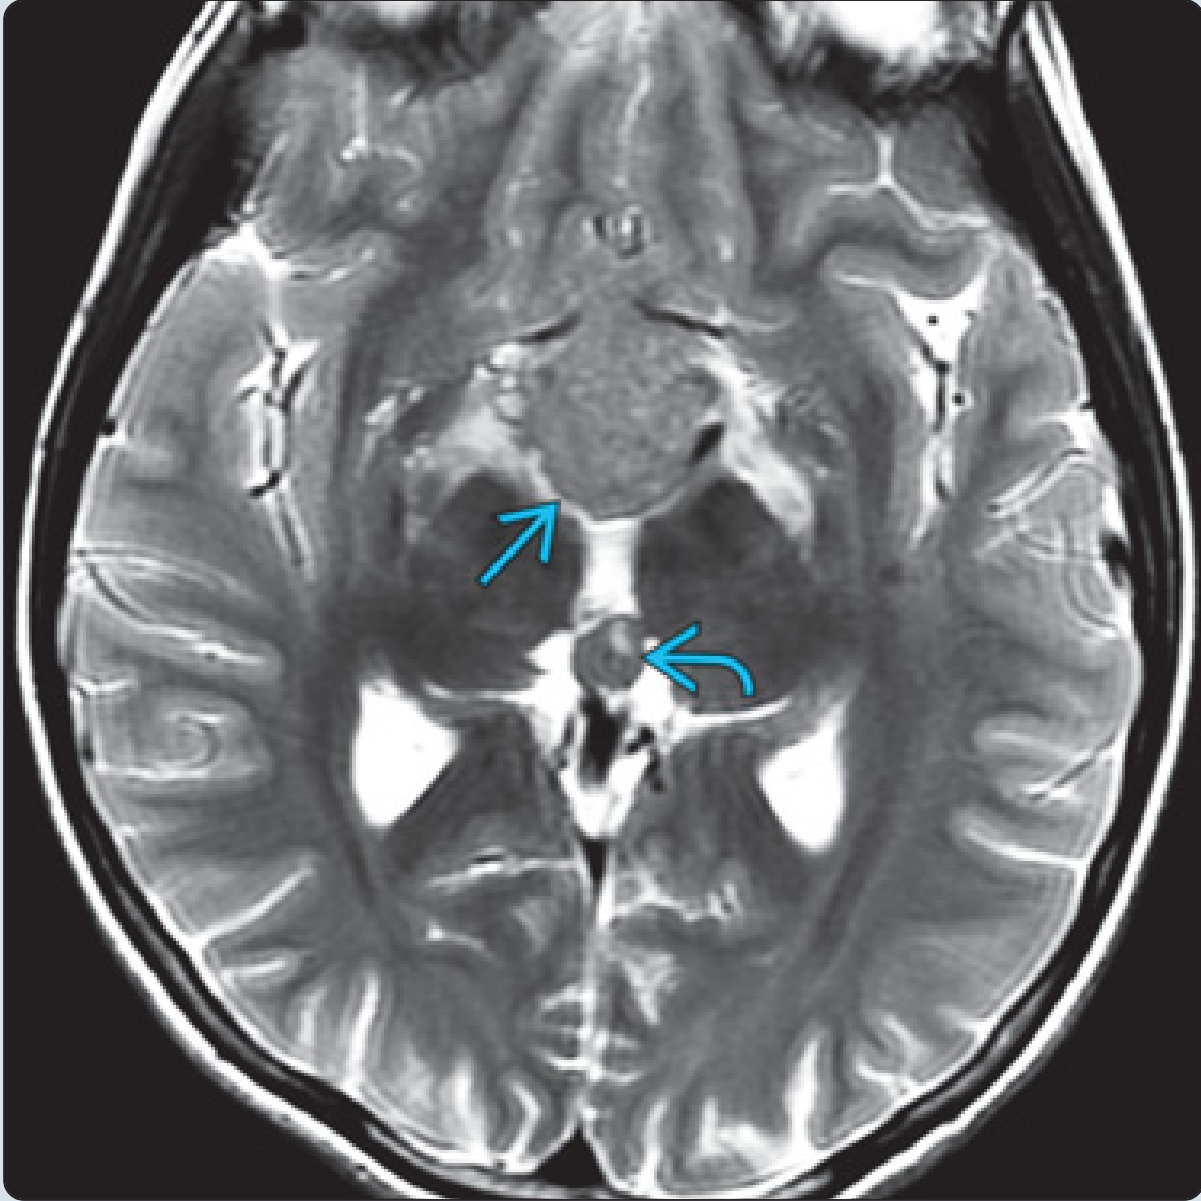

14岁男孩,视力下降,轴位T2WI示鞍上肿块,相对于灰质呈稍低信号。第二个较小的肿块存在于松果体。